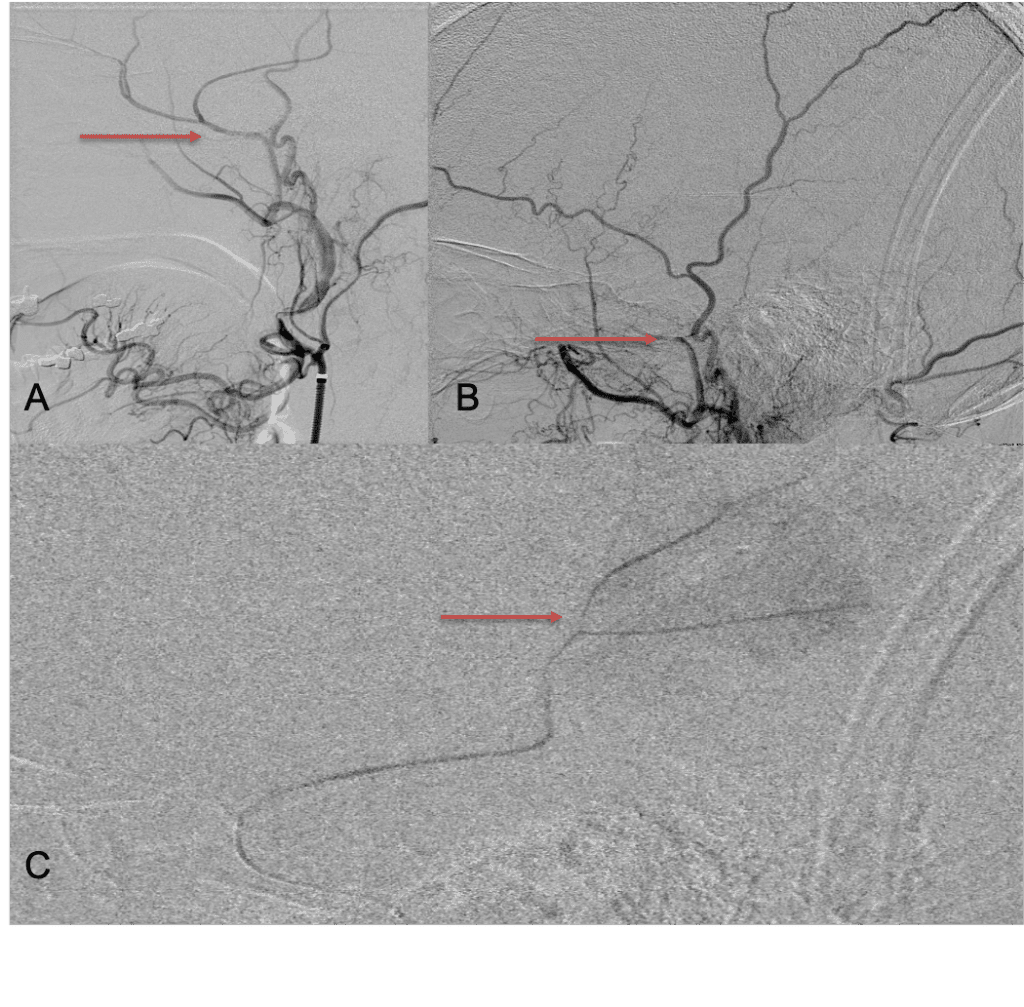

CT follow-up at 1 week demonstrates early resorption. 2 weeks post MMA embolization, resolution of the left subdural collection with new small thin acute hemorrhage in an otherwise stable right subdural collection is observed (Figure 3. A and B).

Figure 3. A) 1 week post MMA embolization demonstrating decreasing thickness bilaterally B) 2 weeks post MMA demonstrates resolution on left, with small new acute component on right with overall decreased thickness.